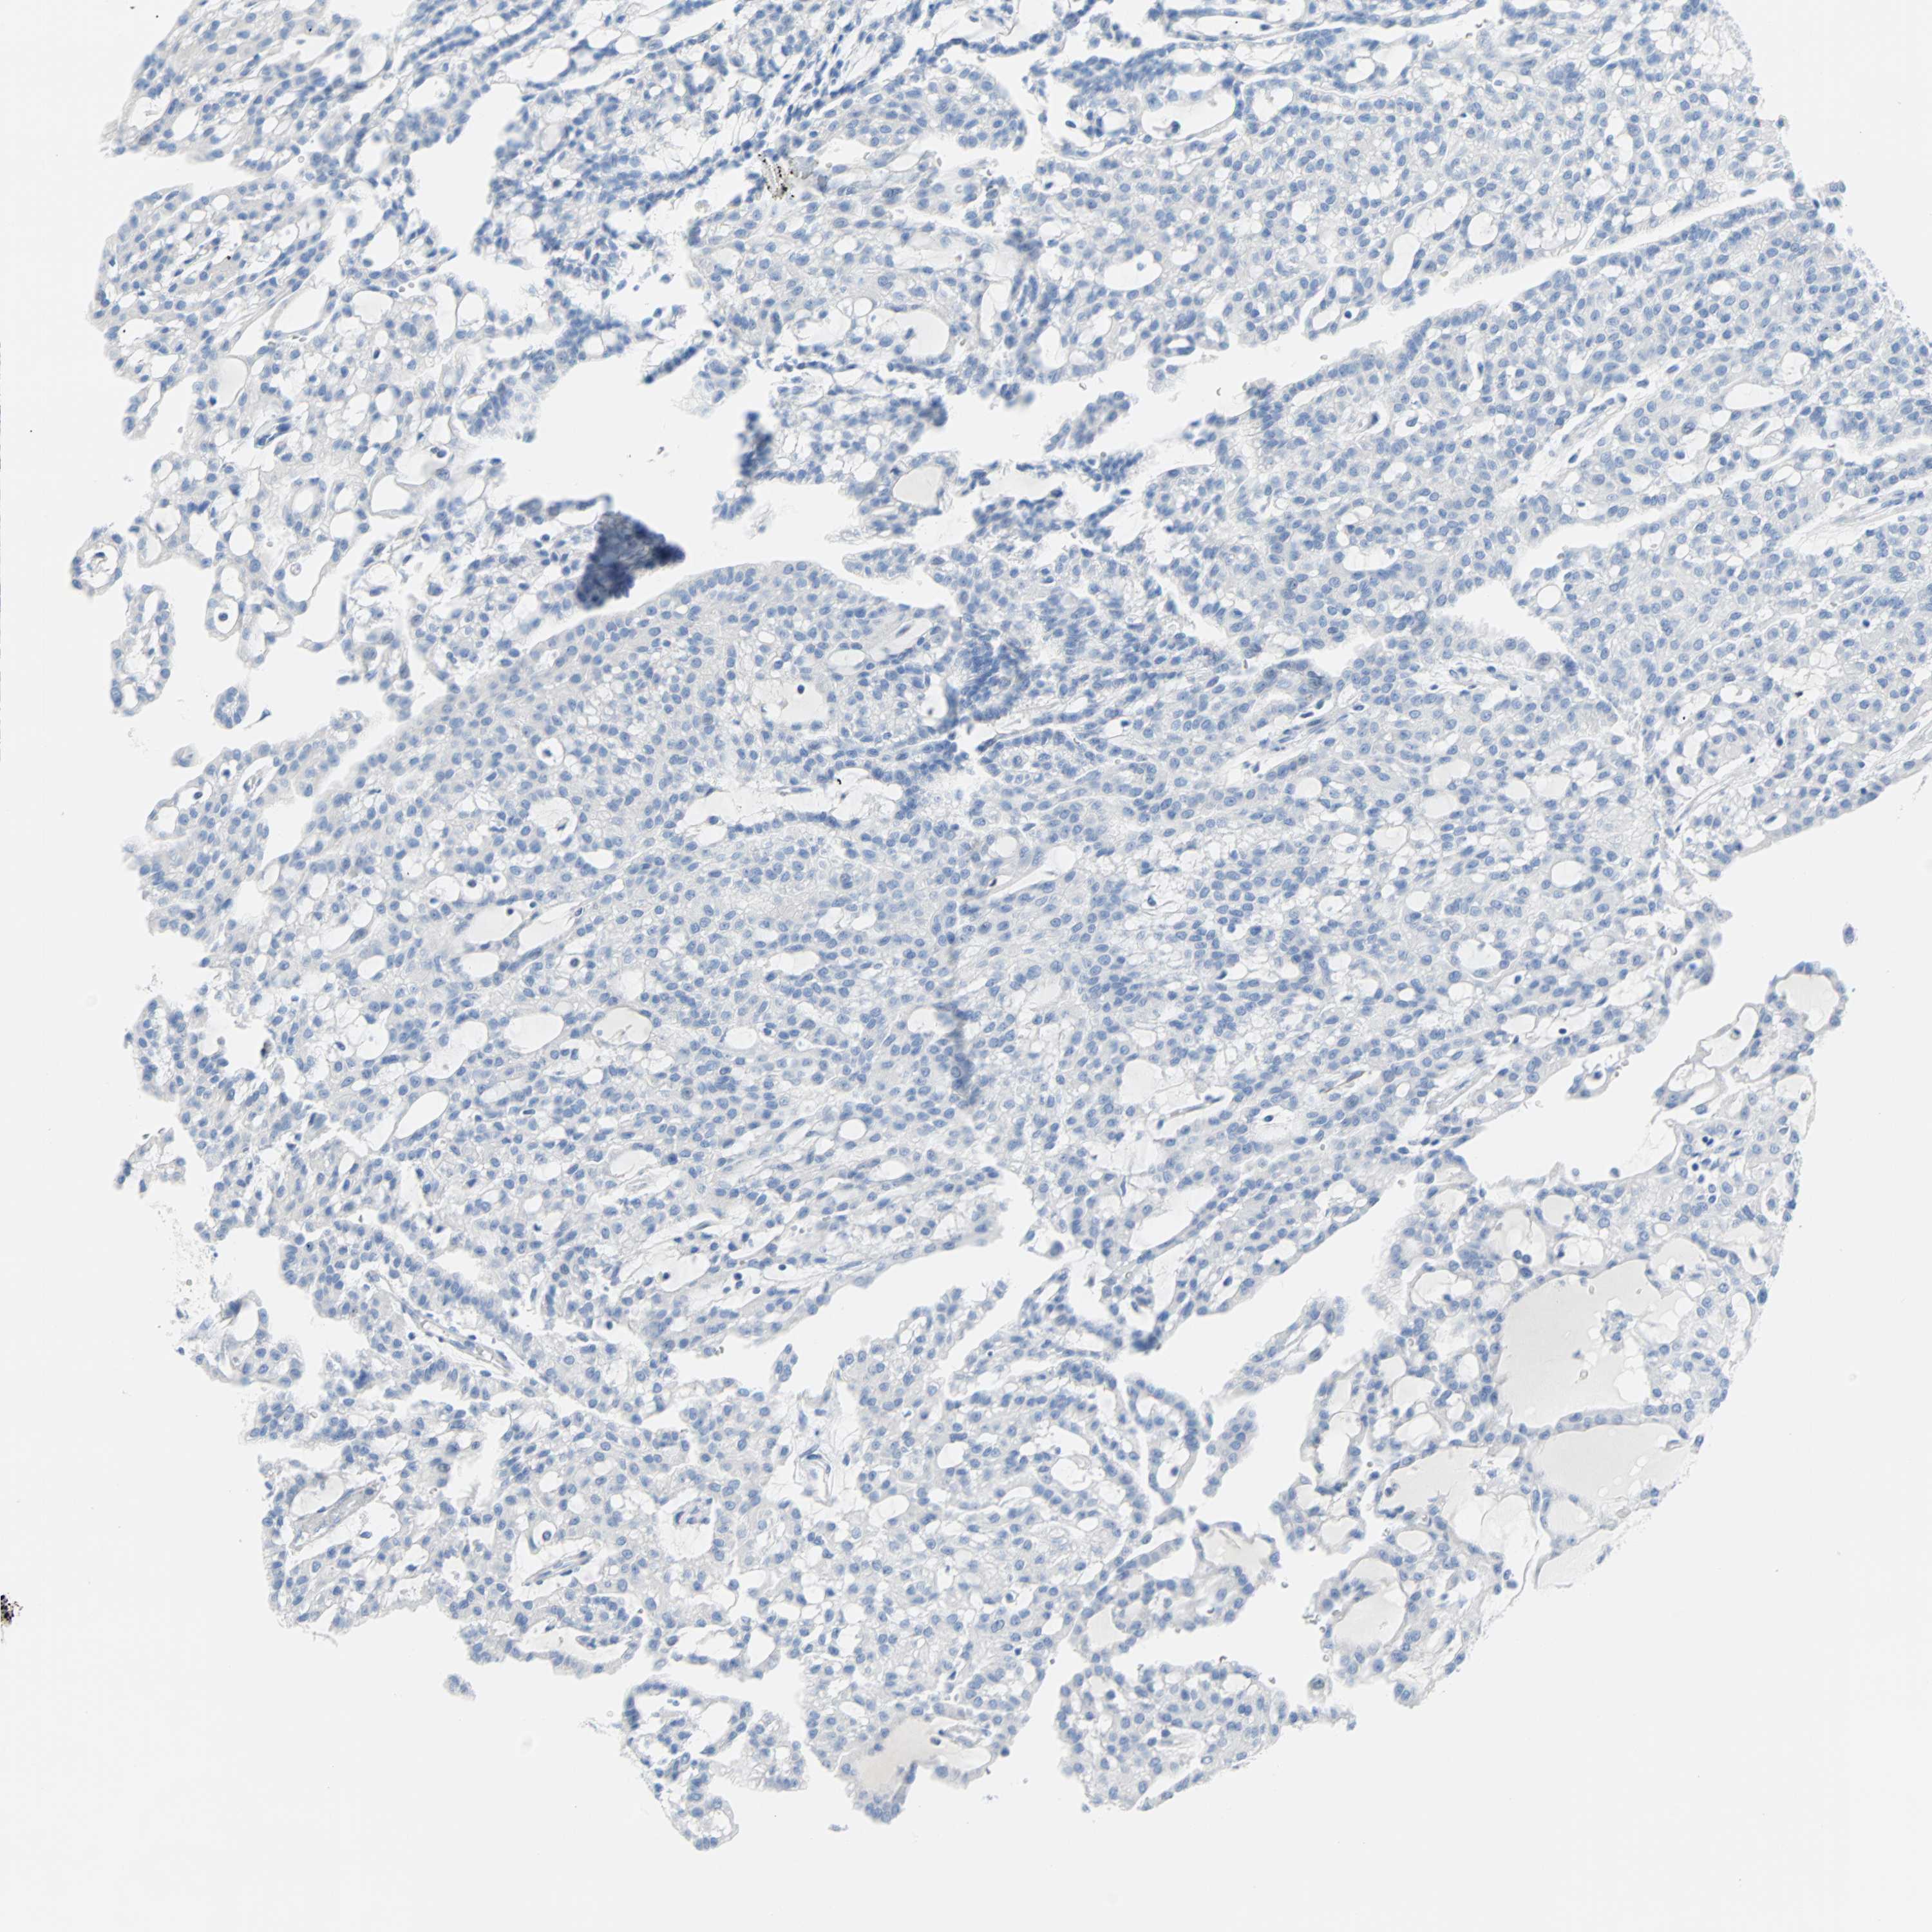

Renal cancer

Human cancer

Kidney chromophobe

Kidney renal clear cell carcinoma

Kidney renal papillary cell carcinoma